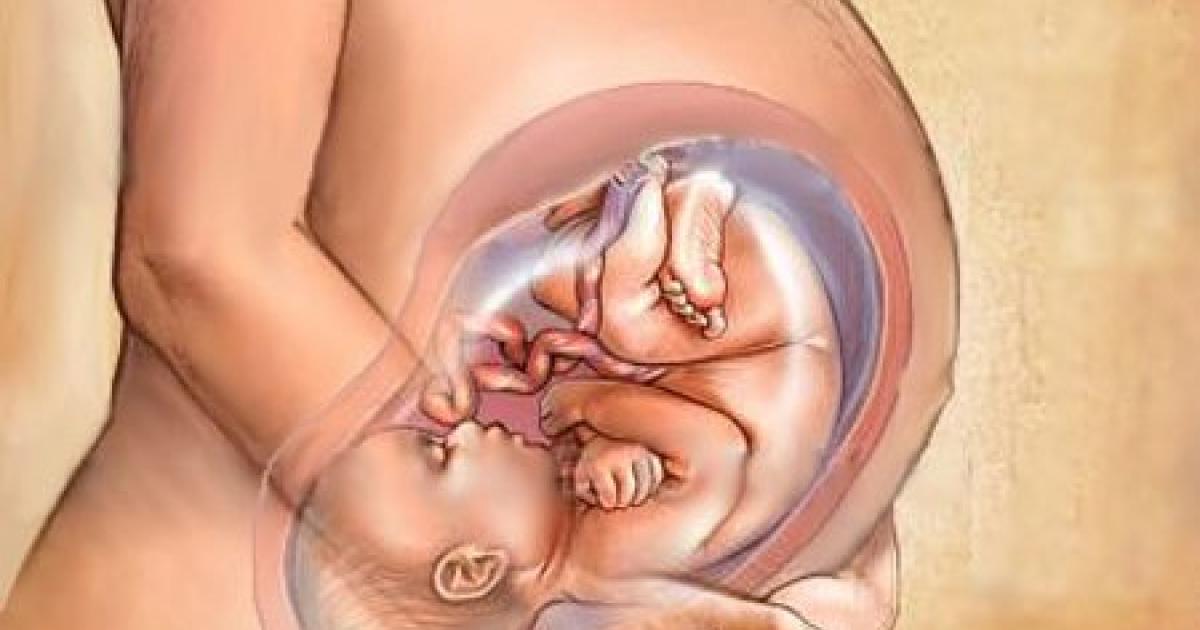

Плод 39 Недель Фото

Плод 39 Недель Фото 100 фото